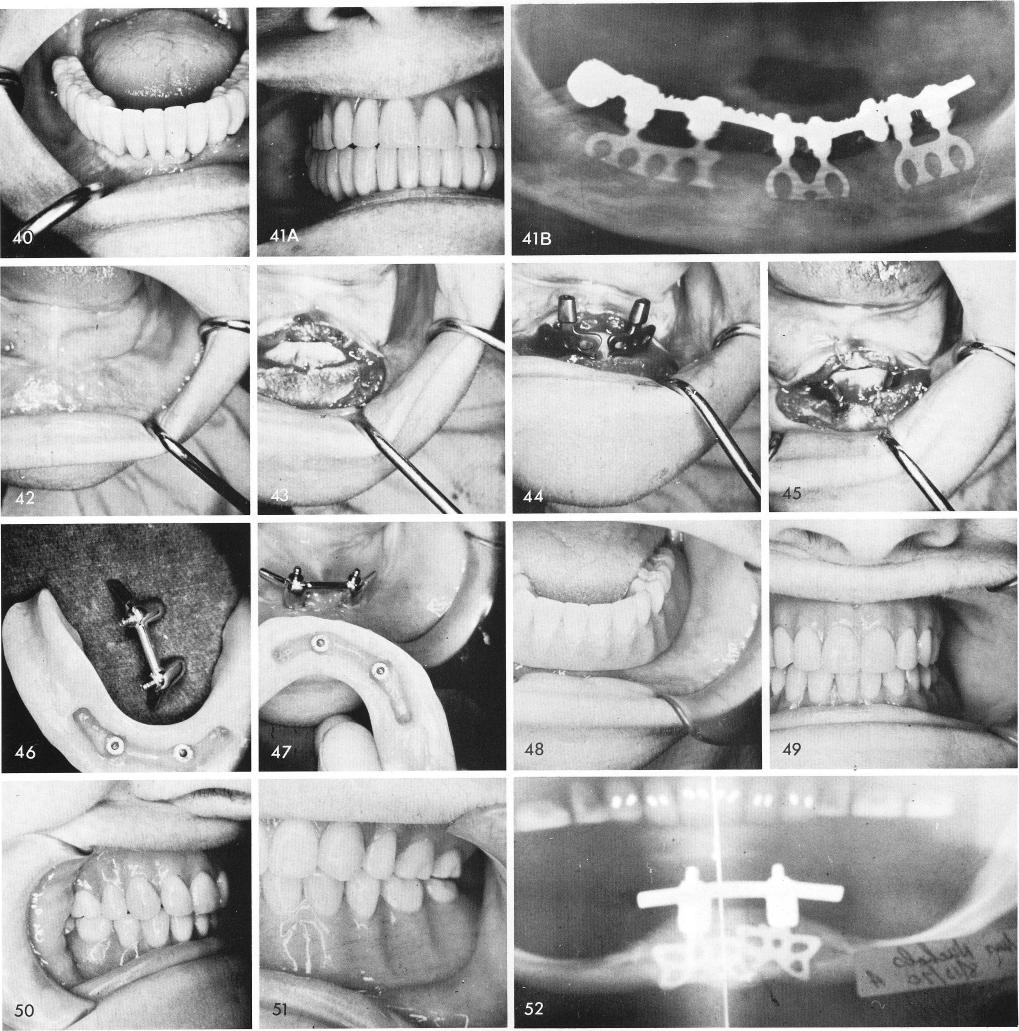

the periodontally involved left cuspid, fig. 38. Another full arch fixed restoration was inserted and cemented, figs. 39, 40, 41A, 41B.

Sometimes, but not too often, in a totally edentulous mandible, fig. 42, the insertion of two anterior blades, figs. 43, 44, 45, can be enough to stabilize a denture, especially when no bone exists posteriorly. Splinting the blades to each other with a Dolder bar with resilient Gerber attachments, figs. 46, 47, to take the pressure off of the implants, can sometimes serve the purpose, figs. 48, 49, 50, 51. A post-operative x-ray of the case, fig. 52.